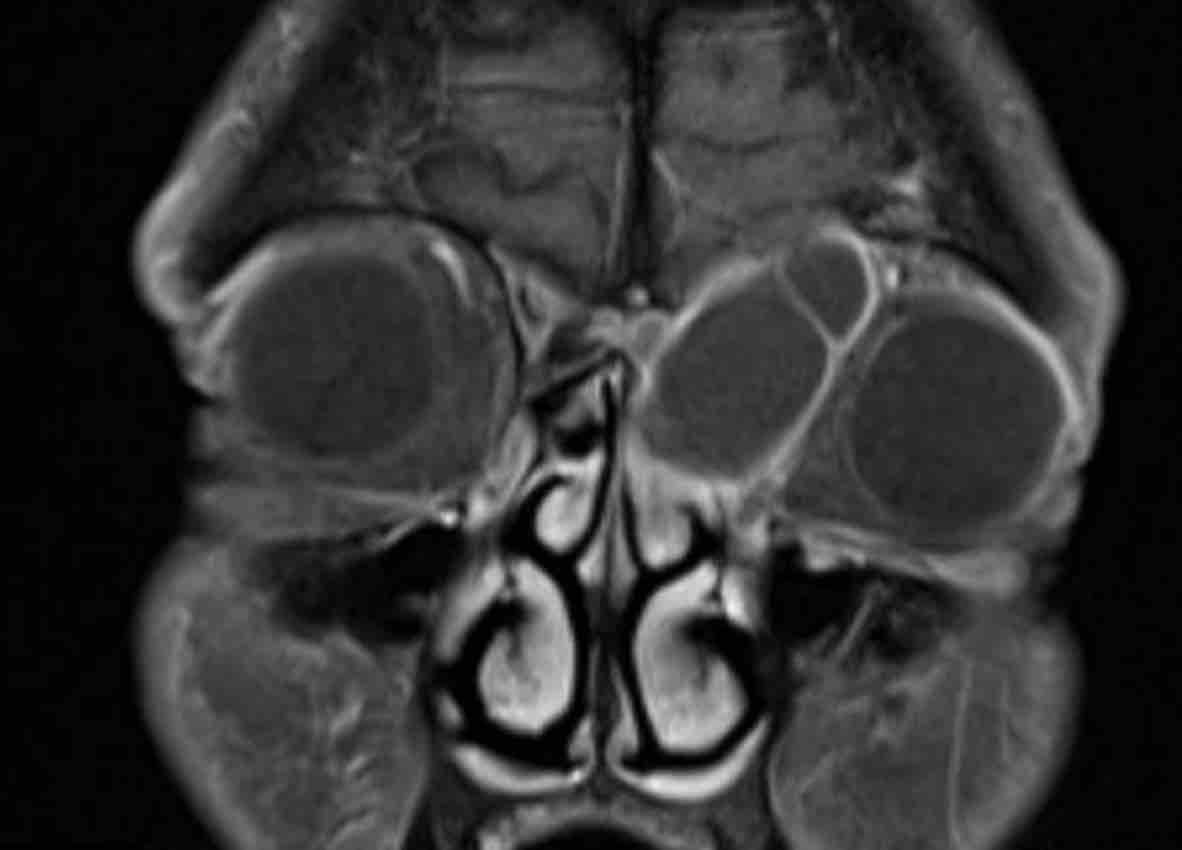

Các hình ảnh này của một bệnh nhân nam 16 tuổi với biểu hiện lồi mắt và chảy máu mũi.

Trên các hình ảnh này, có một tổn thương phá hủy xương với xâm lấn vào hốc mắt.

MRI cho thấy một khối u phá hủy một bên với hạn chế khuếch tán rõ rệt (giảm tín hiệu trên bản đồ ADC).

Như vậy, chúng ta có ba dấu hiệu cảnh báo.

Hạn chế khuếch tán là một lập luận khác chống lại chẩn đoán u xơ mạch máu vị thành niên, vì một tổn thương mạch máu sẽ không gây ra hạn chế khuếch tán.

Có xâm lấn vào hốc mắt và cả vào phần mềm phía trước của má (mũi tên).

Sinh thiết được thực hiện và cho kết quả là u cơ vân (rhabdomyosarcoma), được điều trị bằng hóa trị liệu.